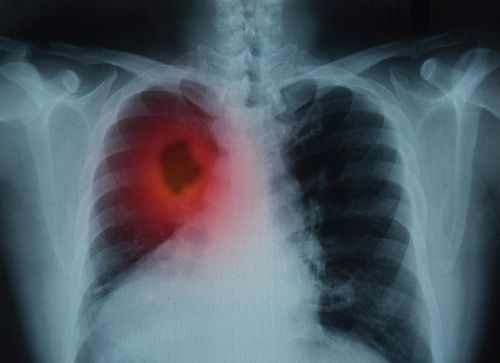

Xray of chest with red mass showing on lefthand side

Radon-Induced Lung Cancer

Radon is a gas that when inhaled, decomposes into radioactive decay products that cause damage to your lungs and can lead to cancer. Radon is a class 'A' carcinogen meaning that there is adequate human data to indicate that it causes cancer in people.

Your chances of getting radon-induced lung cancer depends on how much radon is in your home, the amount of time you are exposed to it, and whether you are a smoker. Long-term radon exposure is the leading cause of lung cancer in non-smokers. There are an estimated 21,000 deaths in the U.S each year due to radon-induced lung cancer.